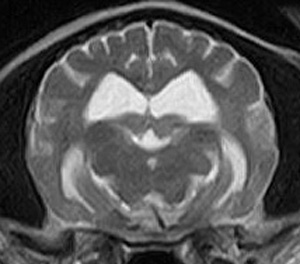

けいれん発作が出るワンちゃんが来院されました。MRI検査では脳に構造上の異常を認めず、特発性てんかんとの診断でお薬での治療となりました。発作は現在のところ、お薬で良好にコントロールされています。